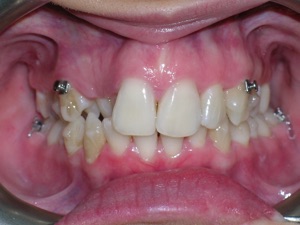

This case was of a young lady who desperately wanted Invisalign, but had been told it was not possible. There was not one, but two teeth that had come in toward the roof of the mouth.

Here are some progress photos.